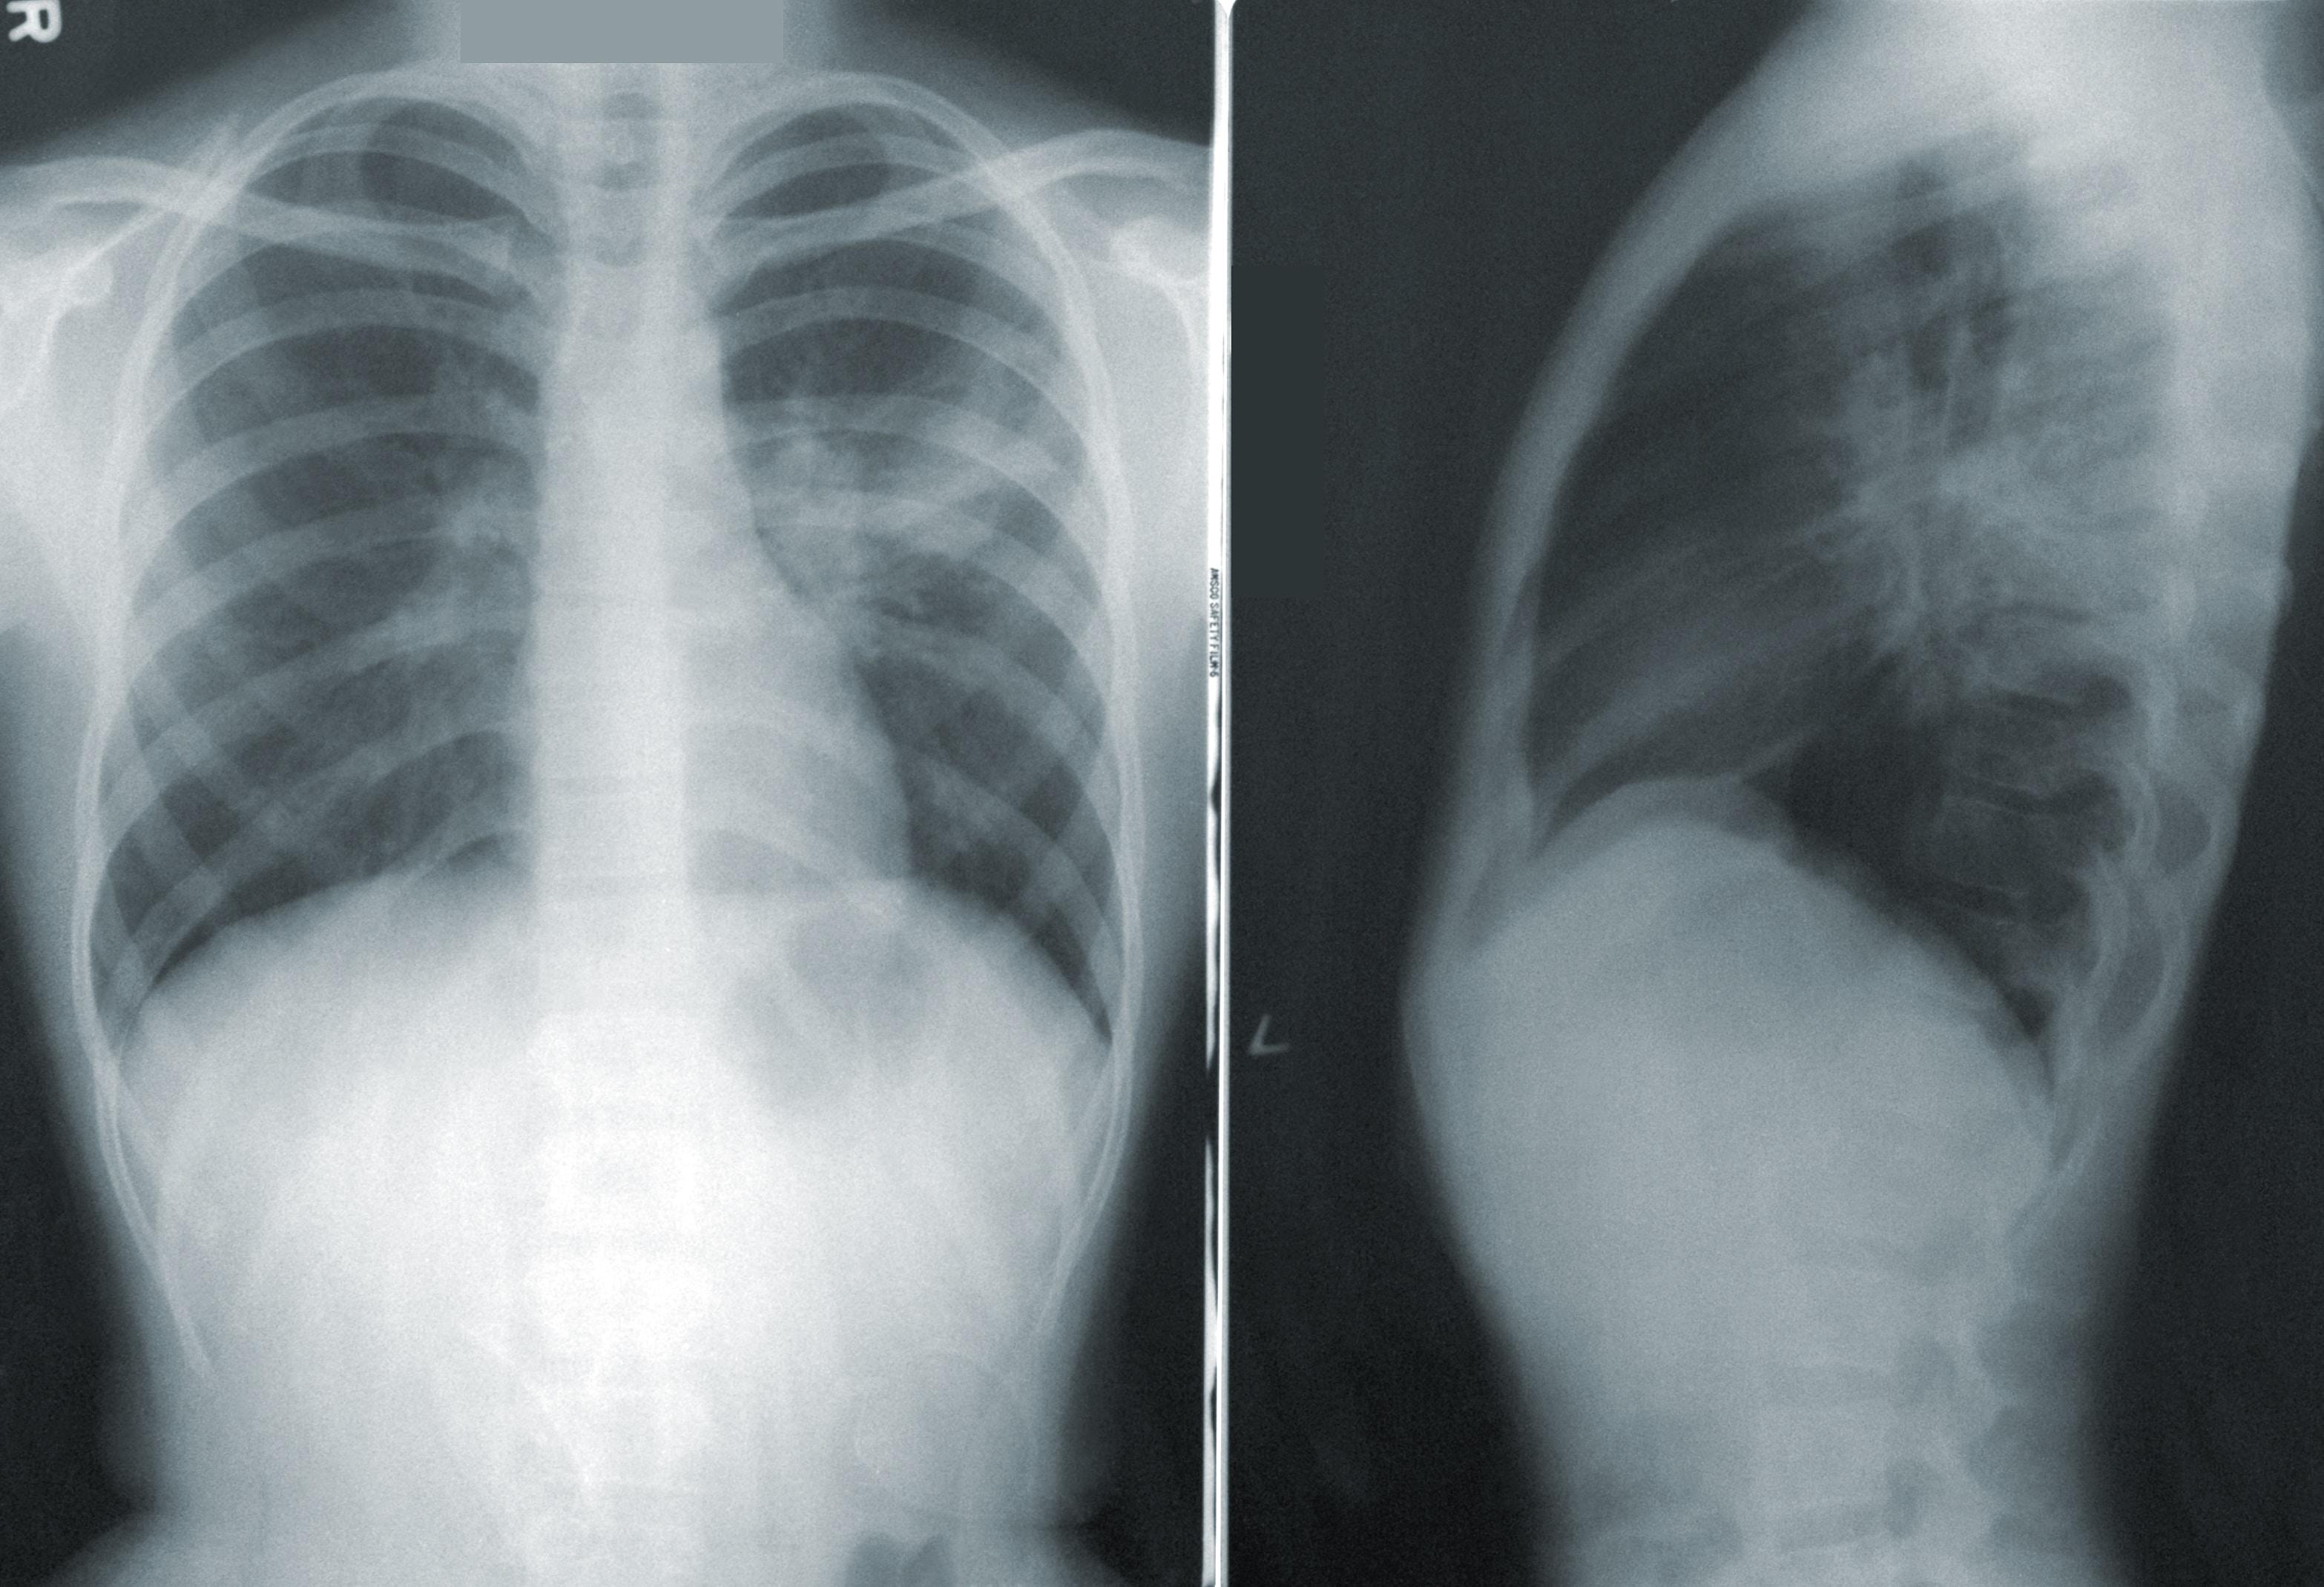

Sprawdź jakie są objawy przewlekłej obturacyjnej choroby płuc